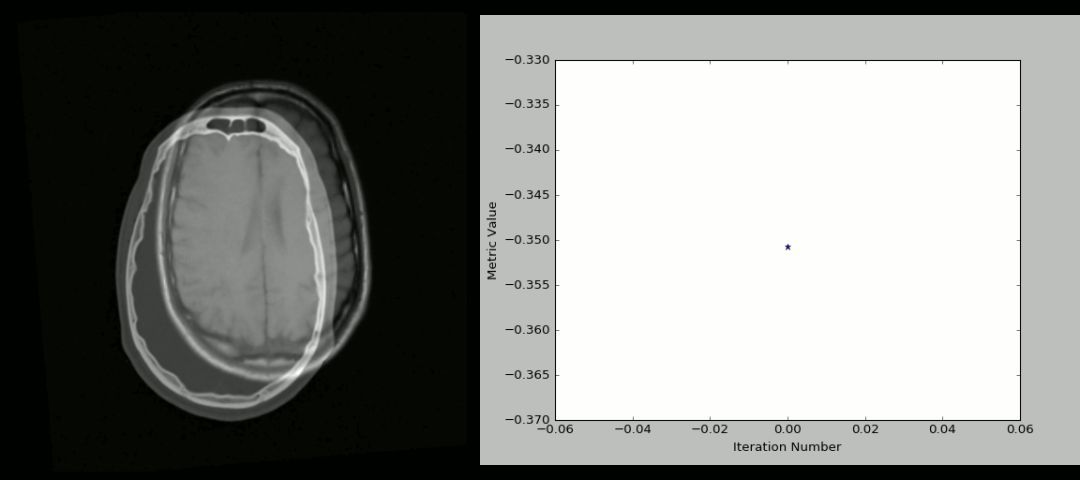

8. SimpleITK

ITK 或者 Insight Segmentation and Registration Toolkit是一个开源的跨平台系统,为开发人员提供了一套广泛的图像分析软件工具 。其中, SimpleITK是建立在ITK之上的简化层,旨在促进其在快速原型设计、教育、解释语言中的应用。SimpleITK 是一个图像分析工具包,包含大量支持一般过滤操作、图像分割和匹配的组件。SimpleITK本身是用C++写的,但是对于包括Python以内的大部分编程语言都是可用的。

资源

大量的Jupyter Notebooks 表明了SimpleITK在教育和研究领域已经被使用。Notebook展示了用Python和R编程语言使用SimpleITK来进行交互式图像分析。

http://insightsoftwareconsortium.github.io/SimpleITK-Notebooks/

用法

下面的动画是用SimpleITK和Python创建的刚性CT/MR匹配过程的可视化 。下面是源码:

https://github.com/InsightSoftwareConsortium/SimpleITK-Notebooks/blob/master/Utilities/intro_animation.py